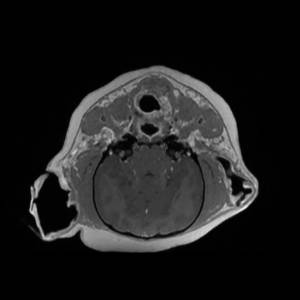

And playing:

Docs: https://www.dokuwiki.org/plugin:photogallery

option fullsize works nicely if all images are the same size.

might want to set the fade between pics to zero?